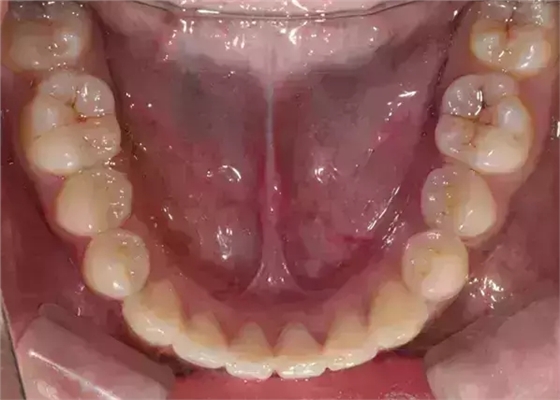

上下牙列擁擠,磨牙尖牙Ⅱ 類關(guān)系,3 度的深覆牙合,上頜中切牙伸長內(nèi)傾拔除上頜雙側(cè)的第一前磨牙,先粘上頜高轉(zhuǎn)矩的自鎖托槽排齊牙列,唇向開展上頜切牙,有一定的覆蓋,粘下頜標準轉(zhuǎn)矩托槽,上頜 1, 2 之間植入種植支抗壓入,同時后牙 5, 6 之間植入種植支抗內(nèi)收前牙,打開咬合關(guān)閉間隙。治療關(guān)鍵:前牙轉(zhuǎn)矩的控制第 1 個月 上頜粘上 Damon Q 高轉(zhuǎn)矩托槽,上 .014 熱激活 NiTi 絲。第 3 個月 上換 .014 x .025 熱激活 NiTi 絲。第 5 個月 上頜基本排齊,覆蓋增大,上換 .017 x .025 NiTi絲,下頜粘托槽,下 .014 熱激活 NiTi 絲。第 7 個月 上 .017 x .025 NiTi 絲加搖椅,下?lián)Q .014 x .025 熱激活 NiTi 絲第 9 個月 上頜換 .019 x .025 NiTi 絲加搖椅,下頜換 .017 x .025 NiTi 絲第 11 個月 下頜換 .019 x .025 加搖椅,上頜 1, 2 之間, 5, 6 之間植入種植釘,下頜出現(xiàn)散隙。第 13 個月 上頜換 .019 x .025ss 加搖椅,前牙種植釘用 Power Chain 壓低前牙(每側(cè) 100g),后牙種植釘關(guān)閉間隙(每側(cè) 150g),下?lián)Q .019 x .025ss,Power Chain 關(guān)閉間隙。第 19 個月 上頜前牙基本壓低到位去除前牙種植釘,繼續(xù)用關(guān)閉間隙,下頜散隙關(guān)閉。